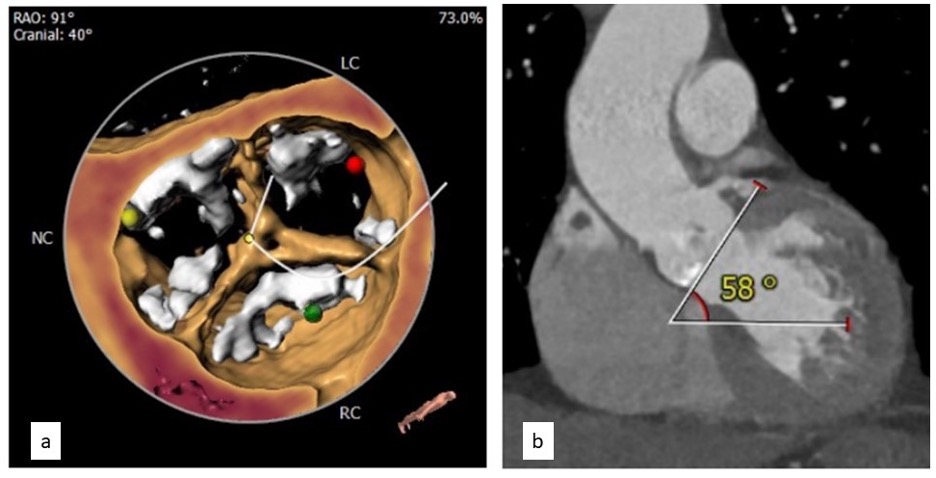

With a Euro SCORE II of 12%, the patient was deemed a high-risk surgical candidate and was prepared for TAVR. Computerized tomography for TAVR evaluation showed a calcified tricuspid aortic valve (Figure 1a) with a mean aortic annulus of 23.1 mm, mean left ventricular outflow tract diameter of 22.3 mm, left coronary height of 14 mm, and right coronary height of 18.6 mm. The patient had bilateral diffuse lower-limb atherosclerosis.

The minimal diameter of the left common iliac artery was 3.1 cm, left external iliac artery was 5 mm, and left common femoral artery was 6.4 mm. The minimal diameter of the right common iliac artery was 7 mm, right external iliac artery was 4 mm, and right common femoral artery was 6.6 mm (Figure 2a). The intimal diameter of the left subclavian was 5 mm (Figure 2b). Annular angulation of 58 degrees added to the challenges (Figure 1b).